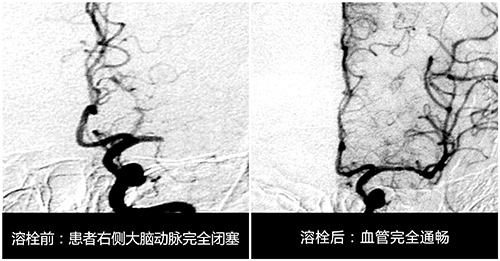

率先组建团队专攻溶栓

孙主任对急性脑梗死溶栓治疗进行了深入的研究,也是当时国内率先开展溶栓研究最早的专家之一。自1995年NINDS研究以后,美国、欧洲、加拿大等国将溶栓治疗超急性期缺血性卒中纳入脑血管病治疗指南,这种方法大大提高了梗死患者治疗的有效性及预后,这鼓舞着孙晓江朝着这个方向继续研究,他也多次参加国际神内学会会议,以撷取先进的理念和方法。

为了更好的进行研究他建立了自己的早期团队,是由他所带的研究生组成。据孙主任介绍,进行溶栓研究的要求是非常严格的,从溶栓治疗患者的选择,到治疗后并发症的预防,再到溶栓治疗的评估,以及影像学诊断与疗效评估,他都建立了一整套体系标准,并要求学生严格按照标准执行,其中最重要的一点是尽可能在“4.5黄金时间窗”内进行溶栓治疗。

1996年11月某天,65岁的张阿姨突发脑梗死,来院时张阿姨脑梗死已病发3—4小时。“当时患者脑梗死情况还是比较严重的,虽然她的意识还算清醒,但右侧肢体已经偏瘫,上肢和下肢的肢体肌力评分几乎为零级,手脚当时一点也不能动,如果不及时进行有效救治,患者不仅会右侧身体偏瘫,还可能会危及生命。”孙主任介绍说。

面对如此紧急的时刻,孙主任第一时间安排患者进行相关检查,随后根据患者的病症及检查结果进行了严格的评估,确定患者符合静脉溶栓的要求。紧接着对患者进行溶栓治疗,经过半小时的精心溶栓后,患者的肢体竟都能动了,病人和家属当时激动得千恩万谢。